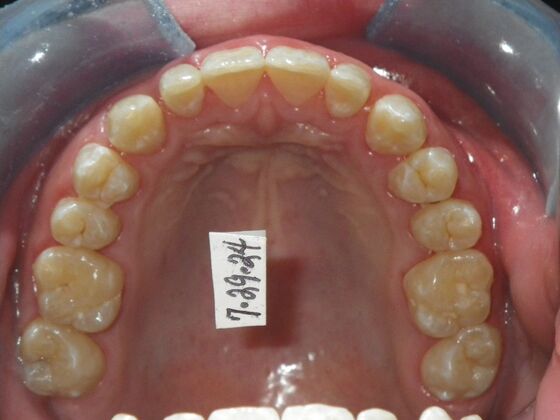

Orthodontic treatment in Phases: Case 12

This patient does not like his anterior deep bite and the flaring of the right lateral incisor as well as anterior spacing. The solution was to correct his Class II molar relationship, Division II and deep anterior bite and close spacing as much as possible with addition of composite restorations on distals of lateral incisors. We began with utility archwires, eventually correcting Class II molar with distalizing appliance, and continued with final tip and torque. All that is left now is to ad composite to distals of upper lateral incisors.